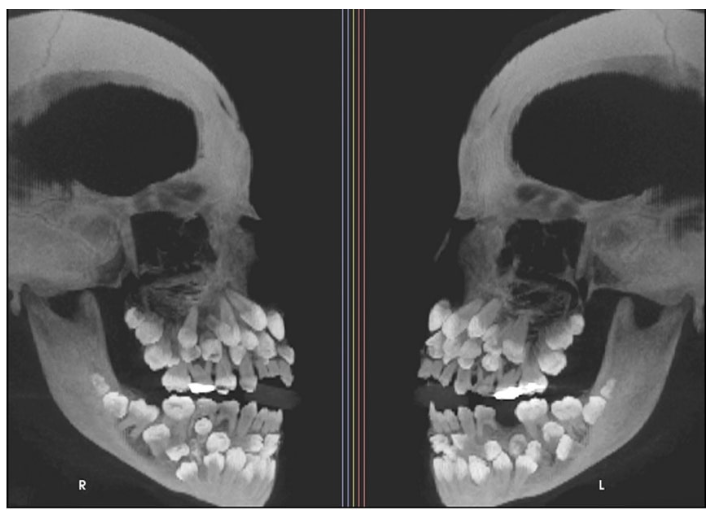

브라질에서 11살 소녀가 유치 한개를 빼기위해 치과 찾았다가

유치18개

영구치 32개

광잉치 31개

총81개 치아가 발견됨 ㄷㄷㄷ